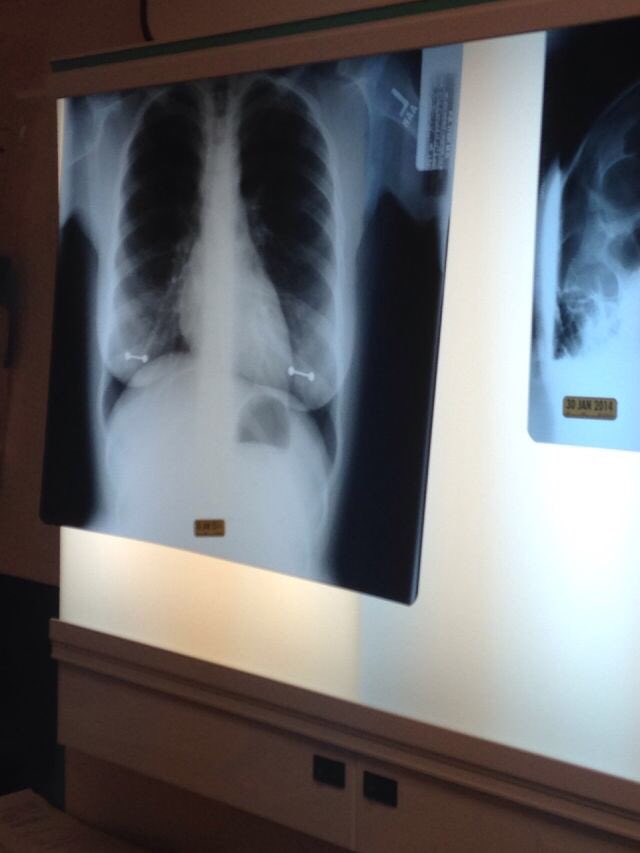

메트로에 따르면 시드니는 척수공동증(Syringomyelia)라는 희귀병을 앓고 있는데 이는 척수 안에 물이 찬 공동이 생기는 병으로, 시간이 지나면서 공동이 커져 척수신경을 손상시킨다.

그래서 시드니의 어머니는 주기적으로 딸을 데리고 병원에 가 엑스레이 검사를 한다고 한다.

그러나 이날 시드니가 피어싱을 빼는 것을 깜빡해 엑스레이에 피어싱이 고스란히 찍히고 말다고 한다.